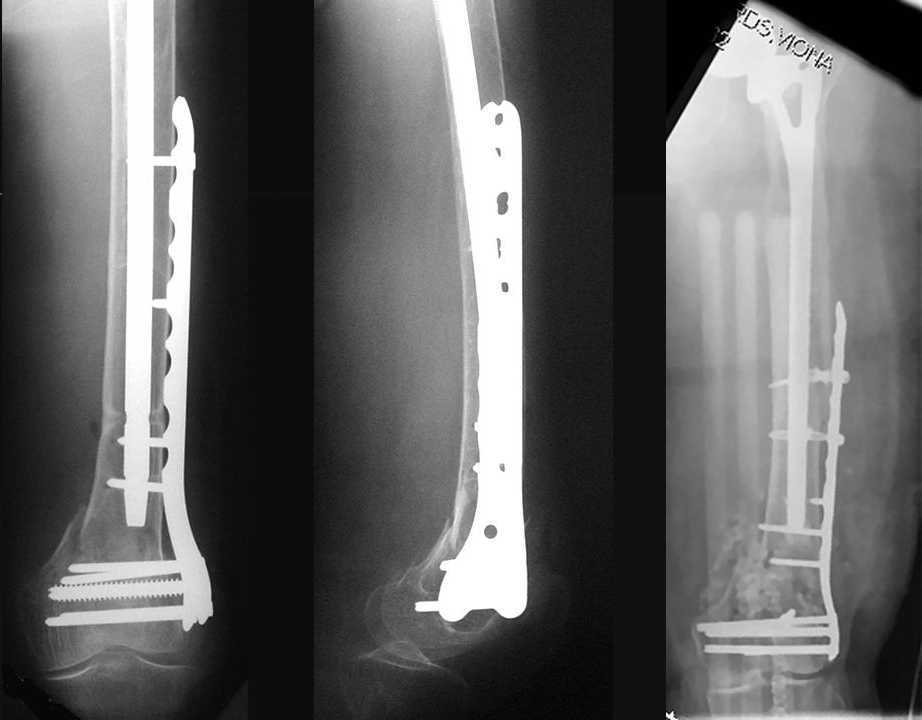

4. We could treat this fracture like there is no a nail - new locking plates allow for secure fixation.... two similar cases are attached...

Images sent by Professor Kanlic look nice, very good job. Excellent achorage in distal fragment. However, unicortical screwing or bicortical

makes a difference, also for locked screws. Proximal fragment unicortical fixation may present stability not easlily predictable. Certainly its stability for wheelchair should be sufficient. Full weight bearing can not be mentioned for this case. If minimal bearing is allowed full weight

single step may happen in elderly.

Our experience with locking plates in osteoporoticbone and weight bearing is that there's no difference with a nail. the old patient start walking with crutches and 20kg weight bearing as the general conditions are good as for the nail. In this case 13 holes LISS with at least 8 cortex proximally

best regards

Images sent by Professor Kanlic look nice, very good job. Excellent achorage in distal fragment. However, unicortical screwing or bicortical makes a difference, also for locked screws. Proximal fragment unicortical fixation may present stability not easlily predictable. Certainly its

stability for wheelchair should be sufficient. Full weight bearing can not be mentioned for this case. If minimal bearing is allowed full weight